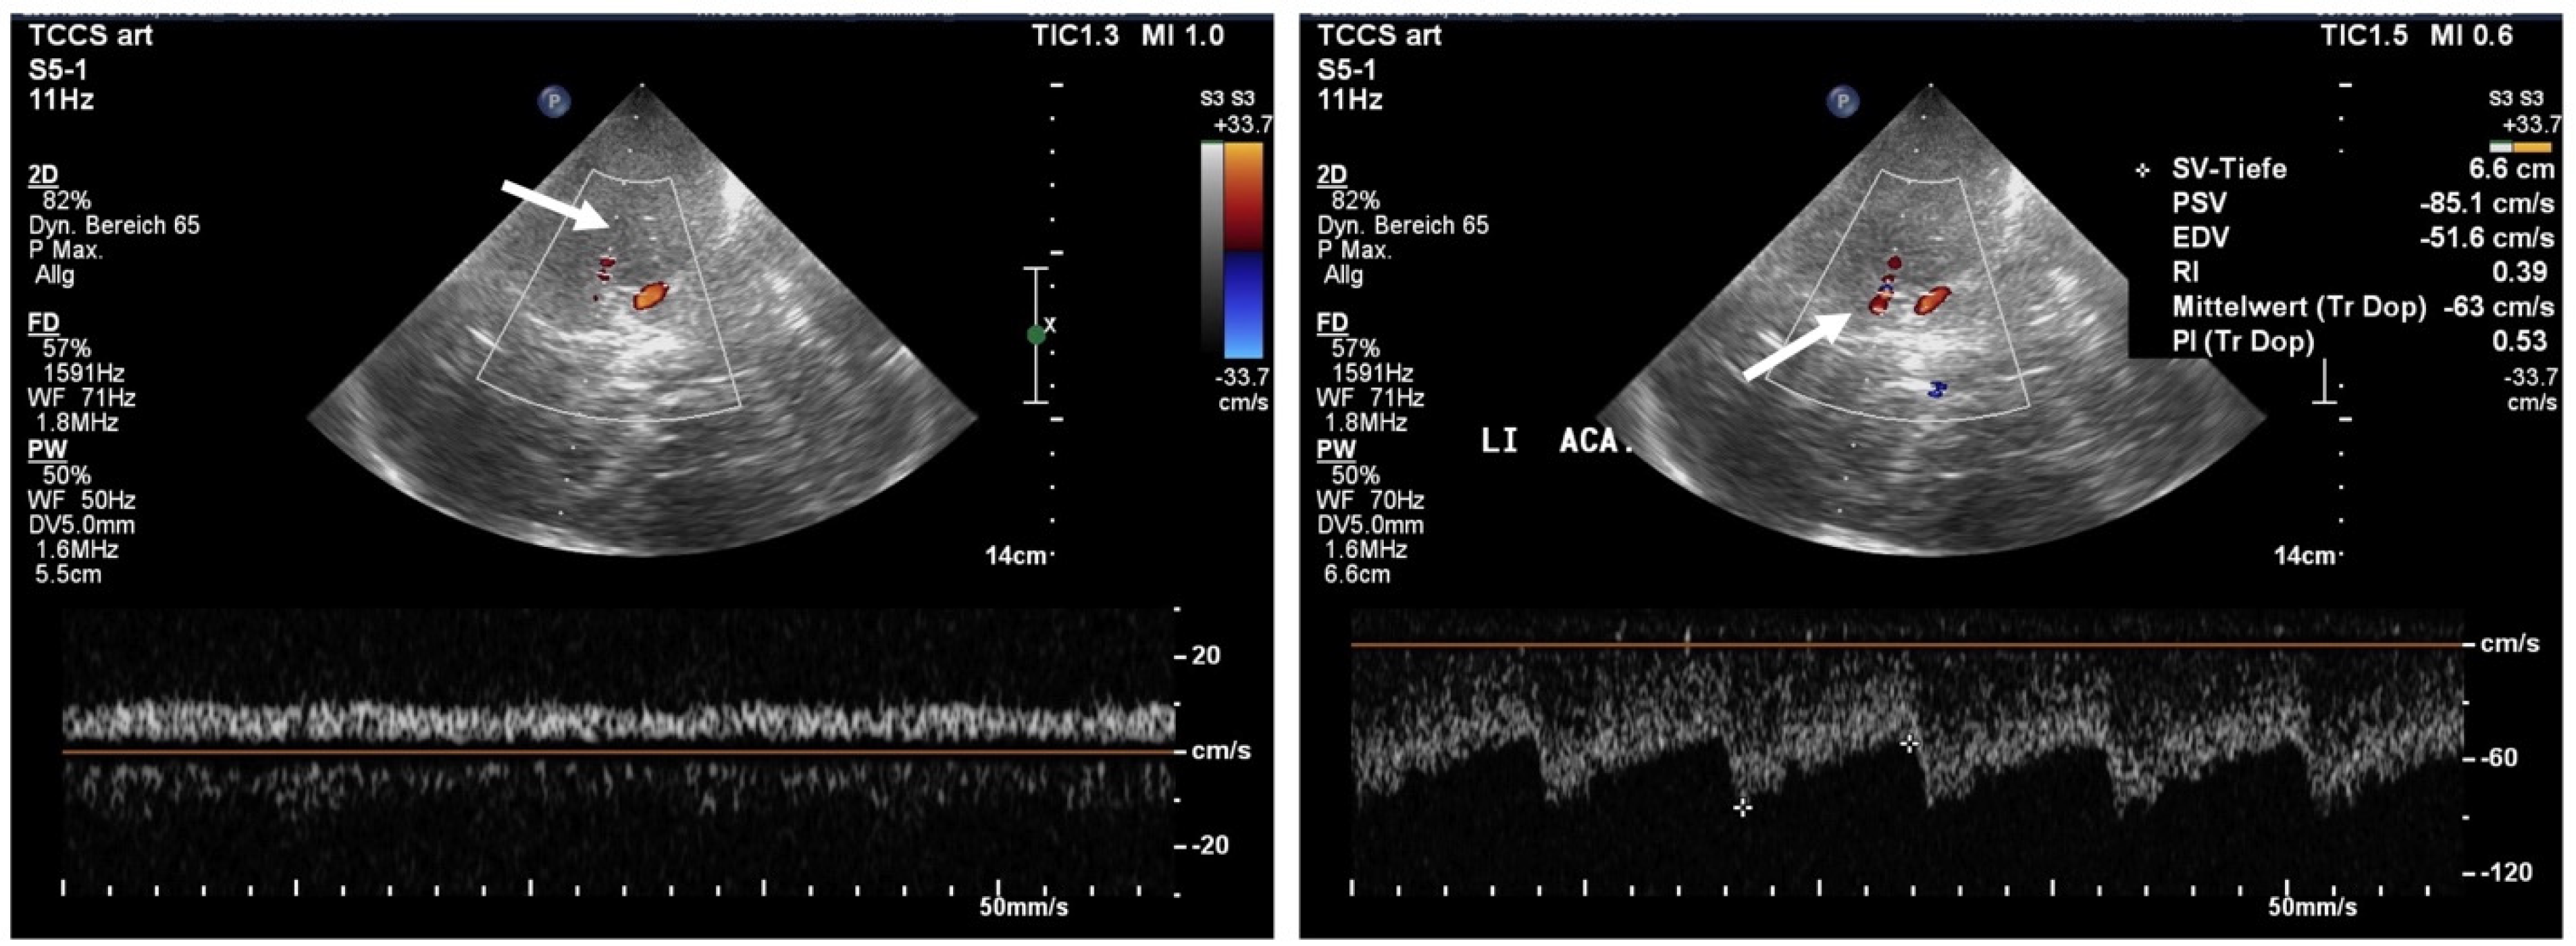

2.2. Transcranial Color-Coded Sonography (TCCS)